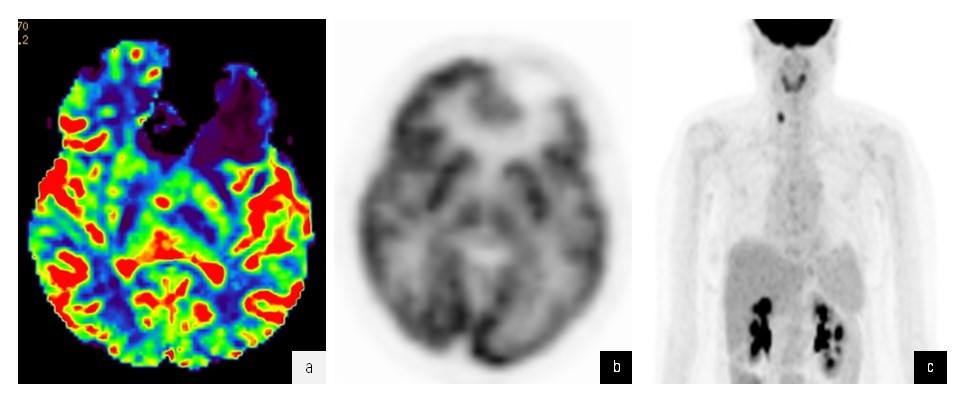

Заключение ПЭТ-КТ 03.10.2022 | Гипоплотная аметаболичная зона лобной доли слева (состояние после хирургического лечения); образования с гиперфиксацией РФП правой доли щитовидной железы неясного генеза; гепатомегалия, жировая инфильтрация печени; жидкостное образование селезенки (рис. 9) |

Рис. 9. a — карта МР-перфузии CBV: отмечается обширная зона гипоперфузии в зоне удаленной опухоли и снижение показателей в зоне отека; б — ПЭТ изображение в аксиальной проекции с 18F-ФДГ: данные коррелируют с МР-перфузией; в — на ПЭТ изображении всего тела 18F-ФДГ выявляется очаг повышенной аккумуляции радиофармацевтического препарата в проекции правой доли щитовидной железы

Fig. 9. a — map of CBV MR perfusion shows an extensive hypoperfusion zone in the area of the removed tumor and a decrease in indicators in the area of edema; б — PET image in axial projection with 18F-FDG data correlate with MR perfusion; в — PET image of the entire body of 18F-FDG reveals a focus of increased accumulation of radiopharmaceutical drug in the projection of the right lobe of the thyroid gland